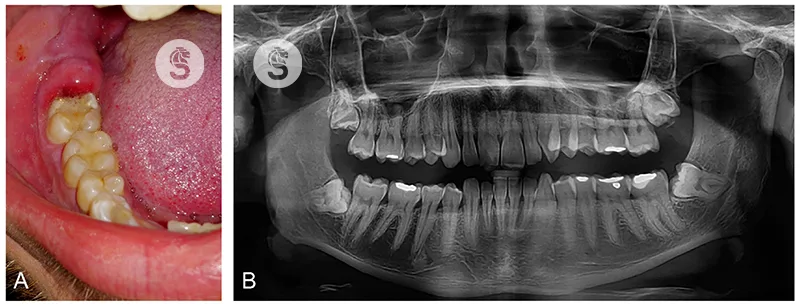

Biện pháp chẩn đoán viêm lợi trùm

Bác sĩ sẽ kết hợp giữa thăm khám lâm sàng và chụp Xquang để xác định viêm lợi trùm.

- Thăm khám lâm sàng: Đầu tiên, bác sĩ sẽ kiểm tra tình trạng của nướu răng. Sau đó, bạn sẽ được hỏi thêm về cảm giác trên răng hiện tại.

- Chụp Xquang: Phương pháp này dùng để xác định cụ thể vị trí răng bị viêm lợi trùm (thường là răng khôn) để làm rõ hơn nguyên nhân bị viêm. Từ đó giúp bạn lên kế hoạch điều trị phù hợp.